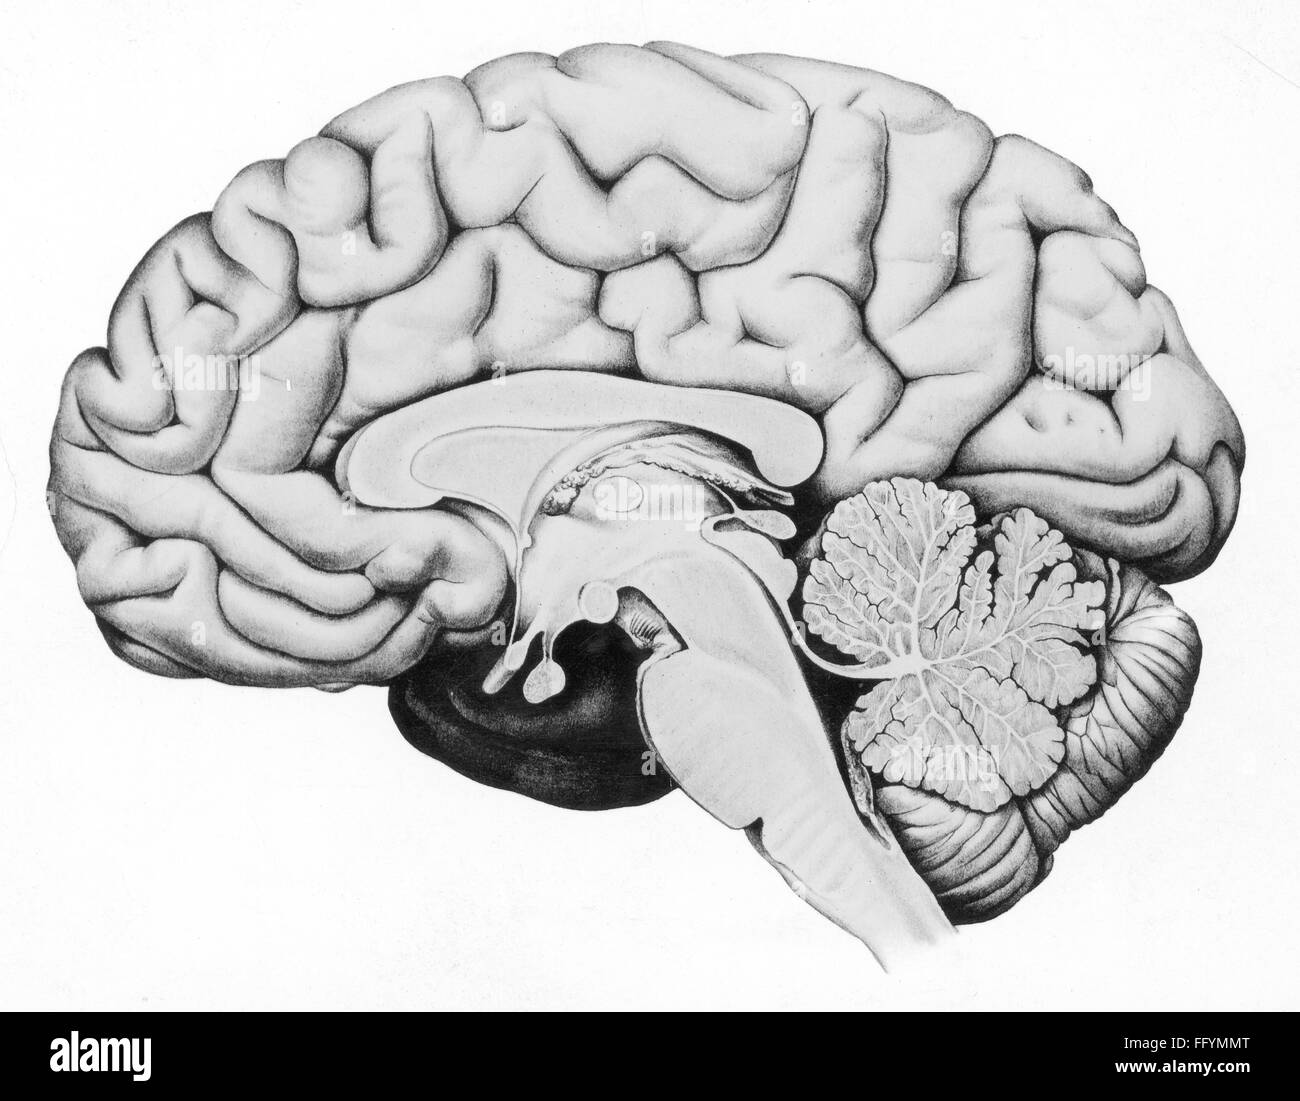

medicine, anatomy, cerebric / cranium, cross section through the human brain, drawing, graphic, graphics, brains, thinking, think, intelligence, personality, personalities, gyri of the brain, cerebrum, cerebellum, mesencephalon, brainstem, medicine, medicines, cross section, cross-section, cross sections, cross-sections, historic, historical, Additional-Rights-Clearences-Not Available Stock Photohttps://www.alamy.com/image-license-details/?v=1https://www.alamy.com/stock-photo-medicine-anatomy-cerebric-cranium-cross-section-through-the-human-95880648.html

medicine, anatomy, cerebric / cranium, cross section through the human brain, drawing, graphic, graphics, brains, thinking, think, intelligence, personality, personalities, gyri of the brain, cerebrum, cerebellum, mesencephalon, brainstem, medicine, medicines, cross section, cross-section, cross sections, cross-sections, historic, historical, Additional-Rights-Clearences-Not Available Stock Photohttps://www.alamy.com/image-license-details/?v=1https://www.alamy.com/stock-photo-medicine-anatomy-cerebric-cranium-cross-section-through-the-human-95880648.htmlRMFFYMMT–medicine, anatomy, cerebric / cranium, cross section through the human brain, drawing, graphic, graphics, brains, thinking, think, intelligence, personality, personalities, gyri of the brain, cerebrum, cerebellum, mesencephalon, brainstem, medicine, medicines, cross section, cross-section, cross sections, cross-sections, historic, historical, Additional-Rights-Clearences-Not Available